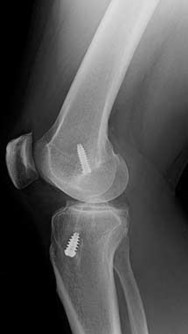

What is the most likely explanation for the change between the initial intraoperative radiograph (Figure 11a) and the radiograph taken 4 weeks after surgery (Figure 11b) in an 87-year-old man who underwent primary hip replacement for osteoarthritis?

The image demonstrates subsidence of the femoral implant. The implant subsided because it did not have good initial stability. The tapered femoral implant was placed after initial preparation for an anatomic femoral stem. A limited, nondisplaced femoral neck fracture was encountered during the procedure and treated. Two advantages of tapered stems are the efficient transfer of stress to the proximal femur and the ability to accommodate some subsidence to achieve enhanced stability. Although subsidence of a tapered stem to a more stable position can produce a good result, quality of metaphyseal bone should be considered. Attention to surgical technique remains important to optimize component stability for biological fixation.